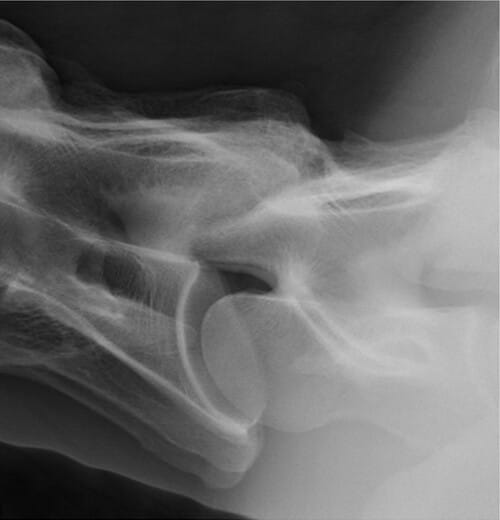

Lateral radiographic image of C6-C7 in which half of the observers considered this image to be consistent with moderate to severe (grade 3) CAPJ OA and half of the observers considered this image to be consistent with mild (grade 2) CAPJ OA. Acquired with 90 kVp, 40 mAs, using a 10:1 grid (Canon, Version 2.16.0.31, Canon, Glen Mills, PA).